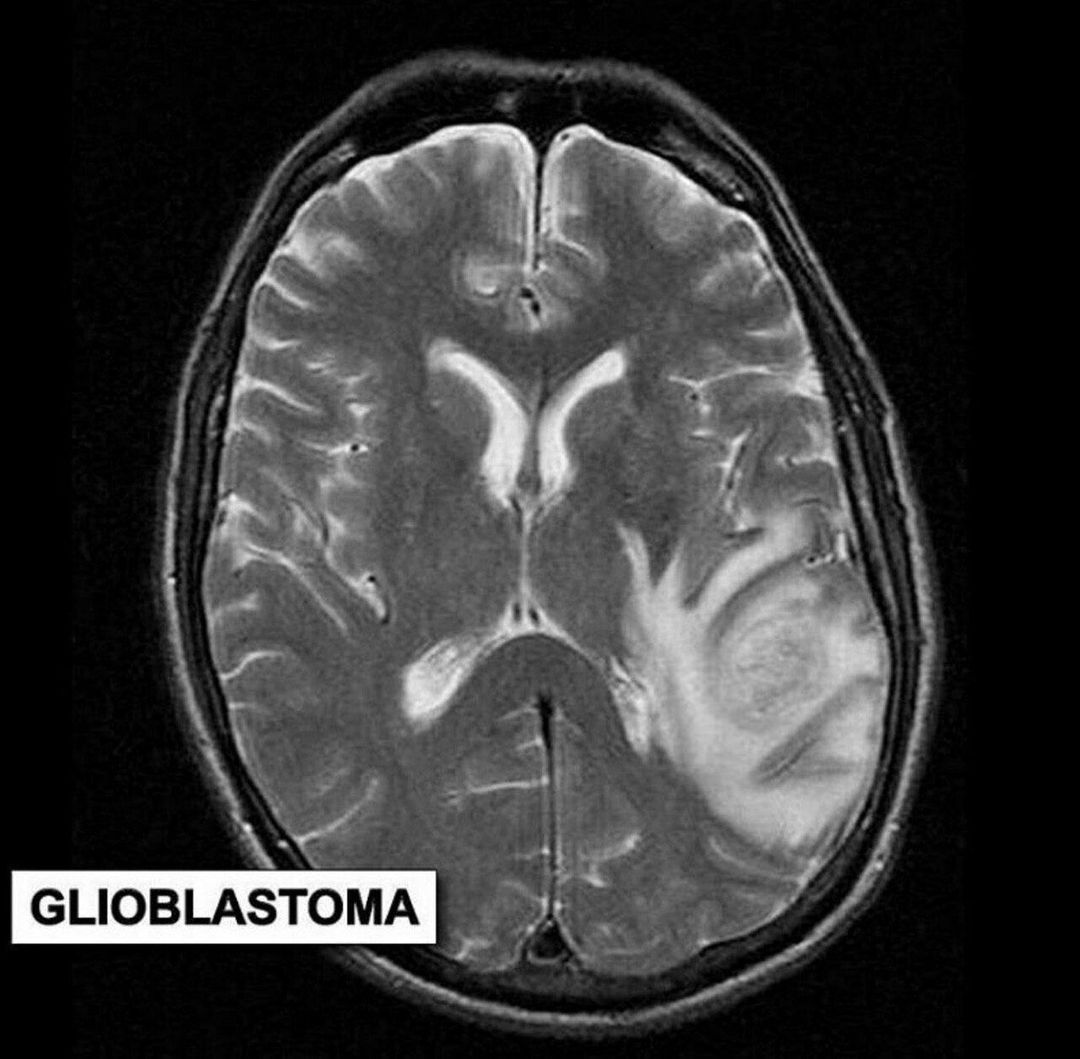

Glioblastoma

Glioblastoma, also known as glioblastoma multiforme (GBM), is the most common and most aggressive cancer that begins within the brain.